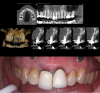

Fig 7. Top right panel: Postoperative radiograph at the 3 month

follow-up visit. Prefabricated coping was picked up and sent for

porcelain. Top left panel: Postoperative insertion photograph at the

3 month follow-up visit. Five-year follow-up periapical radiograph

(bottom left panel) and photograph (bottom right panel) reveal

healthy stable hard and soft tissue.

Three months postoperatively, the patient returned for final impressions. Radiographs and ISQ measurement revealed excellent healing, and intraoral inspection showed proper emergence profiling with adequate soft tissue development. A final impression was performed and a final crown was inserted at the 3 month follow-up visit (Figure 7). Long-term 5-year follow-up revealed excellent stability. The use of CBCT and IOS reduced the duration of treatment and the number of office visits for the patient.